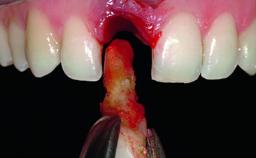

Replacement of a Compromised Upper Right Central Incisor: Hard- and Soft-tissue Augmentation, Late Placement of an RC Bone Level Implant

A 36-year-old male patient with a compromised maxillary central incisor was referred by his general dentist for consultation. The patient’s chief complaints were the gradual debonding of a temporary crown on the right central incisor and unsatisfactory esthetics due to an increasing diastema between the right central and lateral incisors. The patient reported a traumatic event some years previously, when a crown had been placed after root-canal treatment. The referring dentist wanted to provide a new crown restoration, but was concerned about the condition of the residual root. Anamnesis was negative for any other dental or periodontal pathology in the remaining dentition. The patient reported taking no medications: He was a smoker (10 to 15 cigs/day) and had realistic esthetic expectations.

Bone Augmentation Horizontal|Simultaneous|Staged

Augmentation Materials Xenogenous|Membrane

Soft Tissue Grafting Simultaneous

Bone Volume Deficient horizontally, requiring prior grafting